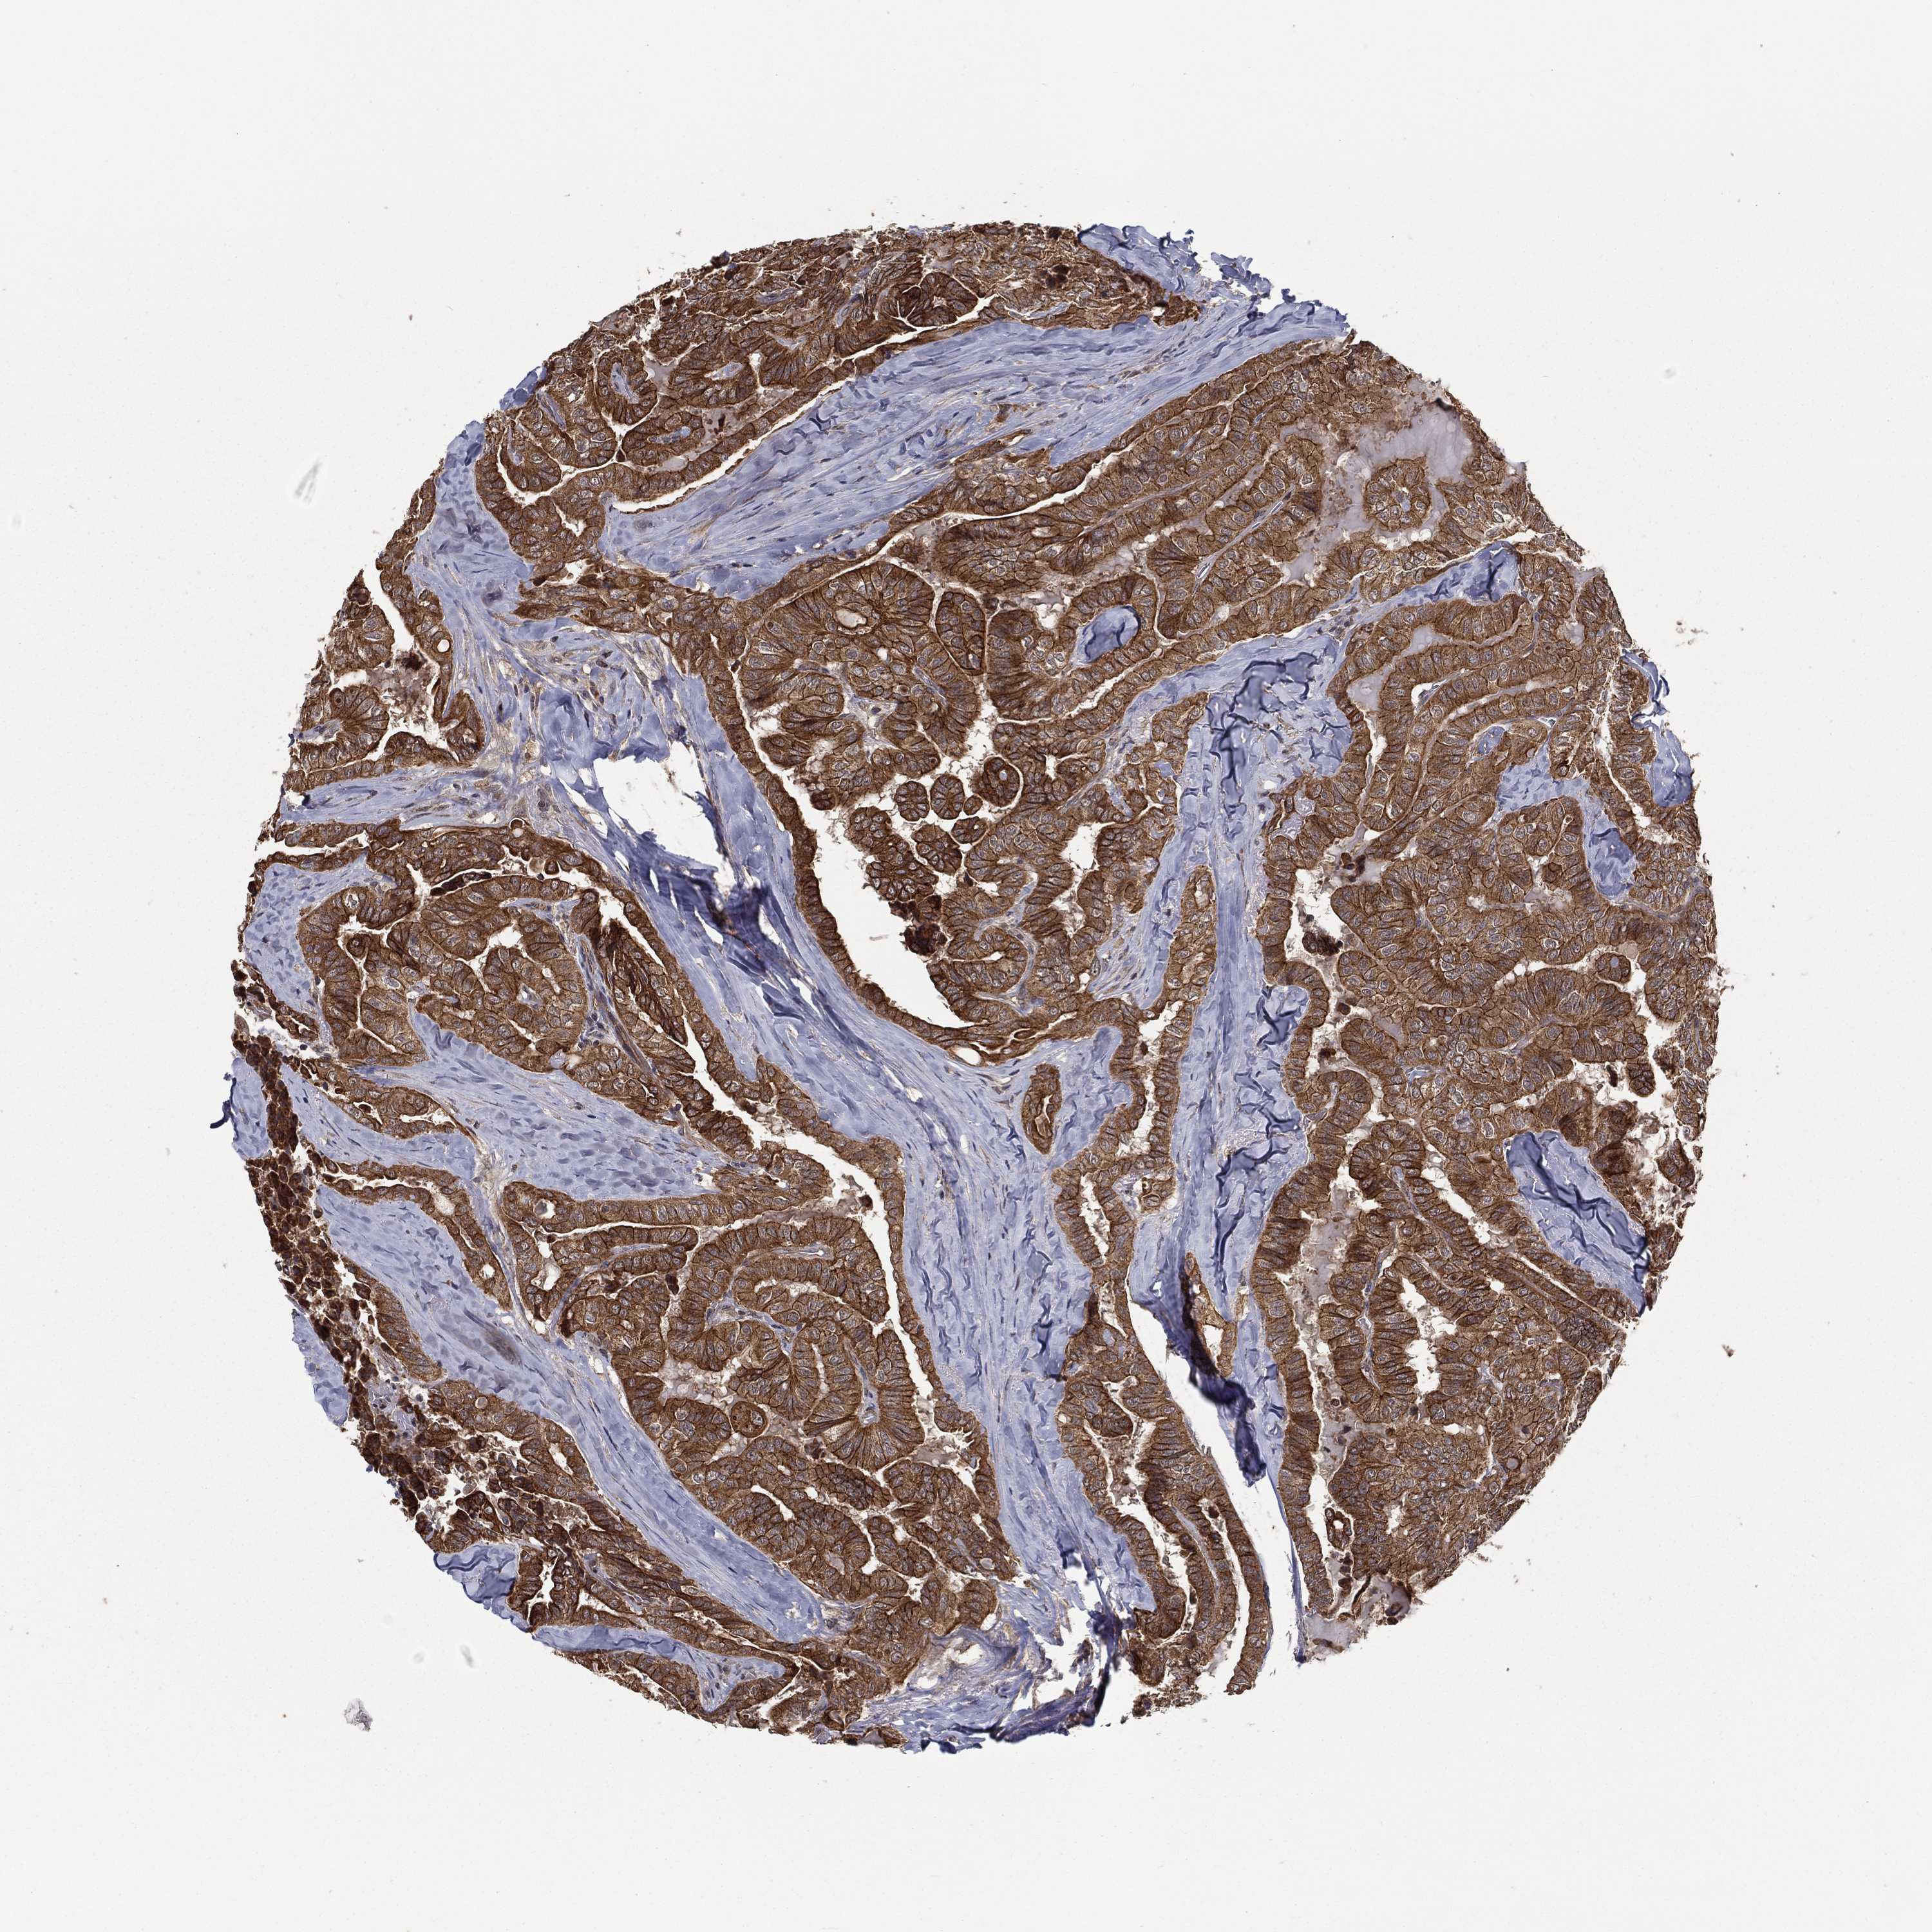

THYROID CANCER - Protein expressioni

A mouse-over function shows sample information and annotation data. Click on an image to view it in a full screen mode. Samples can be filtered based on level of antibody staining by selecting one or several of the following categories: high, medium, low and not detected. The assay and annotation is described here.

Note that samples used for immunohistochemistry by the Human Protein Atlas do not correspond to samples in the TCGA dataset.

Antibody stainingi

Antibody staining in the annotated cell types in the current human tissue is reported as not detected, low, medium, or high, based on conventional immunohistochemistry profiling in selected tissues. This score is based on the combination of the staining intensity and fraction of stained cells.

Each image is clickable and will lead to virtual microscopy that enables deeper exploration of all samples and also displays staining intensity scores, fraction scores and subcellular localization as well as patient and tissue information for each sample.

Antibody HPA041412

Antibody HPA056006

Staining

High

Medium

Low

Not detected

Intensity

Strong

Moderate

Weak

Negative

Quantity

>75%

75%-25%

<25%

None

Location

Nuclear

Cytoplasmic/membranous

Cytoplasmic/membranous,nuclear

Papillary adenocarcinoma, NOS

Follicular adenoma carcinoma, NOS